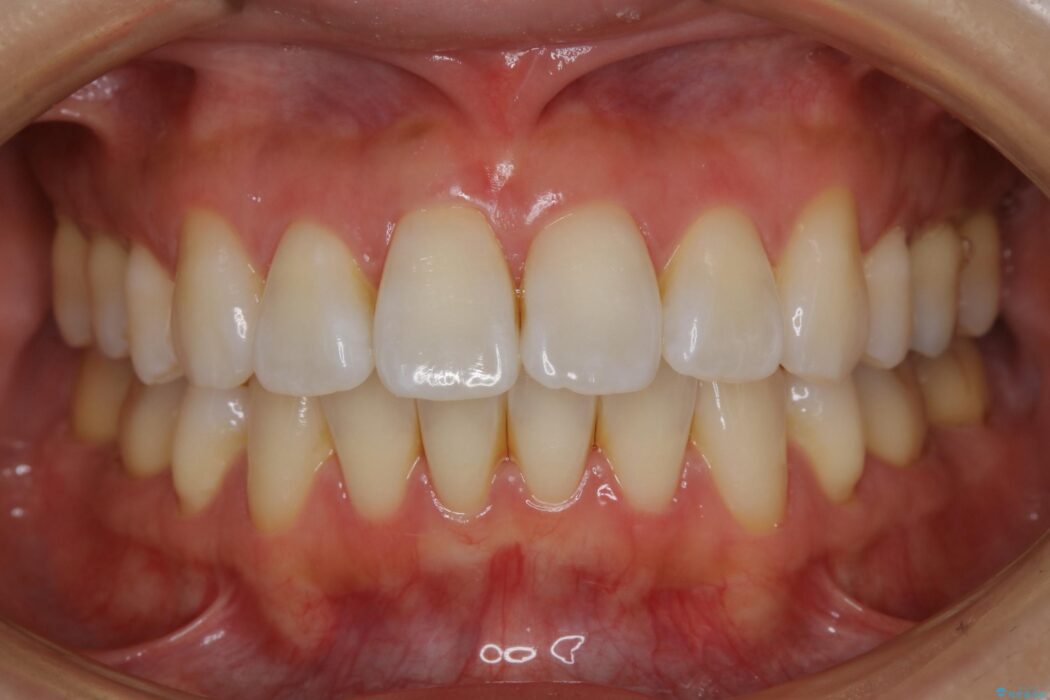

抜歯矯正後の上の前歯の後戻りが気になるとご来院された患者様です。

歯と歯の間を削るのと、歯列のU字型のアーチを僅かに外側に広げる事でスペースを作り、前歯の角度の改善をしました。

保定装置は、マウスピースと前歯の裏側を細いワイヤーで固定(ボンディングリテーナー)を併用していただいてます。